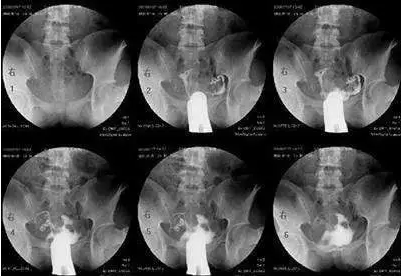

当然,以上说的都是可能性的症状,并不代表有这些症状就一定是输卵管有问题的。如果有这些症状,要适度警惕一下。当然,您也不需要太担忧,最好还要结合多种情况综合考虑,如果实在不放心,可以去医院做做输卵管造影术,或者做输卵管通水、腹腔镜检查、输卵管镜检查等。

最常用的是输卵管碘油造影(HSG)

医生会根据不孕的时间、可能的原因,来选择是否需要做造影。

造影的时间一般在月经干净后3天到排卵之前,造影前不要有性生活,白带检查正常等等。造影后1周禁性生活,当月最好不要尝试怀孕。